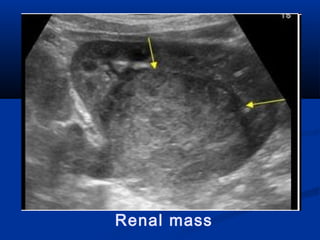

 U/S:U/S: The initial imaging procedure of choiceThe initial imaging procedure of choice

 Reliable for differentiation ofReliable for differentiation of solidsolid tissue fromtissue from

fluidfluid (cyst) and can establish the diagnosis of a(cyst) and can establish the diagnosis of a

simple renal cystsimple renal cyst..

 It can also allow the diagnosis of anIt can also allow the diagnosis of an

angiomyolipomaangiomyolipoma by the characteristic increasedby the characteristic increased

echogenicity produced by high fat content.echogenicity produced by high fat content.

 Sonographic criteria forSonographic criteria for simple cystssimple cysts include:include: 1-1-

smooth cyst wall,smooth cyst wall, 2-2- round or oval shaperound or oval shape 3-3-

without internal echoes (clear fluid)without internal echoes (clear fluid) 4-4- NoNo

calcification nor septationcalcification nor septation

Renal mass